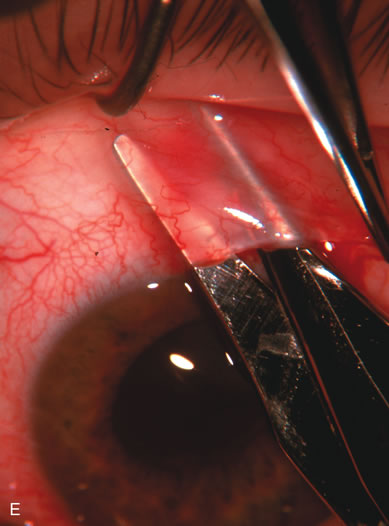

Fig. 4. Viscocanalostomy with deep sclerectomy and phacoemulsification. Nonpenetrating filtration procedures (NPFS) may be combined with phacoemulsification. Patients with mild disc damage and a history of limited topical drug therapy are the best candidates. Patients who require an IOP in the low teens are not good candidates for NPFS. By definition, NPFS is designed to lower IOP without penetrating into the anterior chamber, thereby avoiding the complications associated with trabeculectomy. Viscocanalostomy is intended to allow aqueous to percolate through a trabeculodescemetic membrane into a subscleral cavern created by the deep sclerectomy. The aqueous diffuses from the cavern into the dilated ostia of Schlemm's canal and into the episcleral venous plexus. A. Fashion a uniform 300-micron superficial scleral flap 1 mm into clear cornea. B. Construct a second 600-micron deep flap that facilitates the unroofing of Schlemm's canal, seen as the darker area. C. Use viscoelastic to dilate the ostia of Schlemm's canal. The major problem with viscocanalostomy is the eventual closure of the ostium decreasing flow to the episcleral plexus. D. Dissect the deep flap anteriorly into clear cornea creating the trabeculodescemetic membrane. This membrane is clearly seen between the scleral spur and the bend of the deep flap. The integrity of this membrane ensures the nonpenetrating portion of the surgery. Another problem with NPFS is the eventual fibrosis of this initially transparent membrane requiring goniopuncture. E. Deep sclerectomy gets its name from removal of the deep flap. Removal of this flap creates the potential subscleral space for accumulation of aqueous before it enters Schlemm's canal and exits the episcleral venous plexus. After removal of the deep flap, the superficial flap is sutured into place and conjunctiva closed. Approximately half of these procedures develop a shallow bleb.